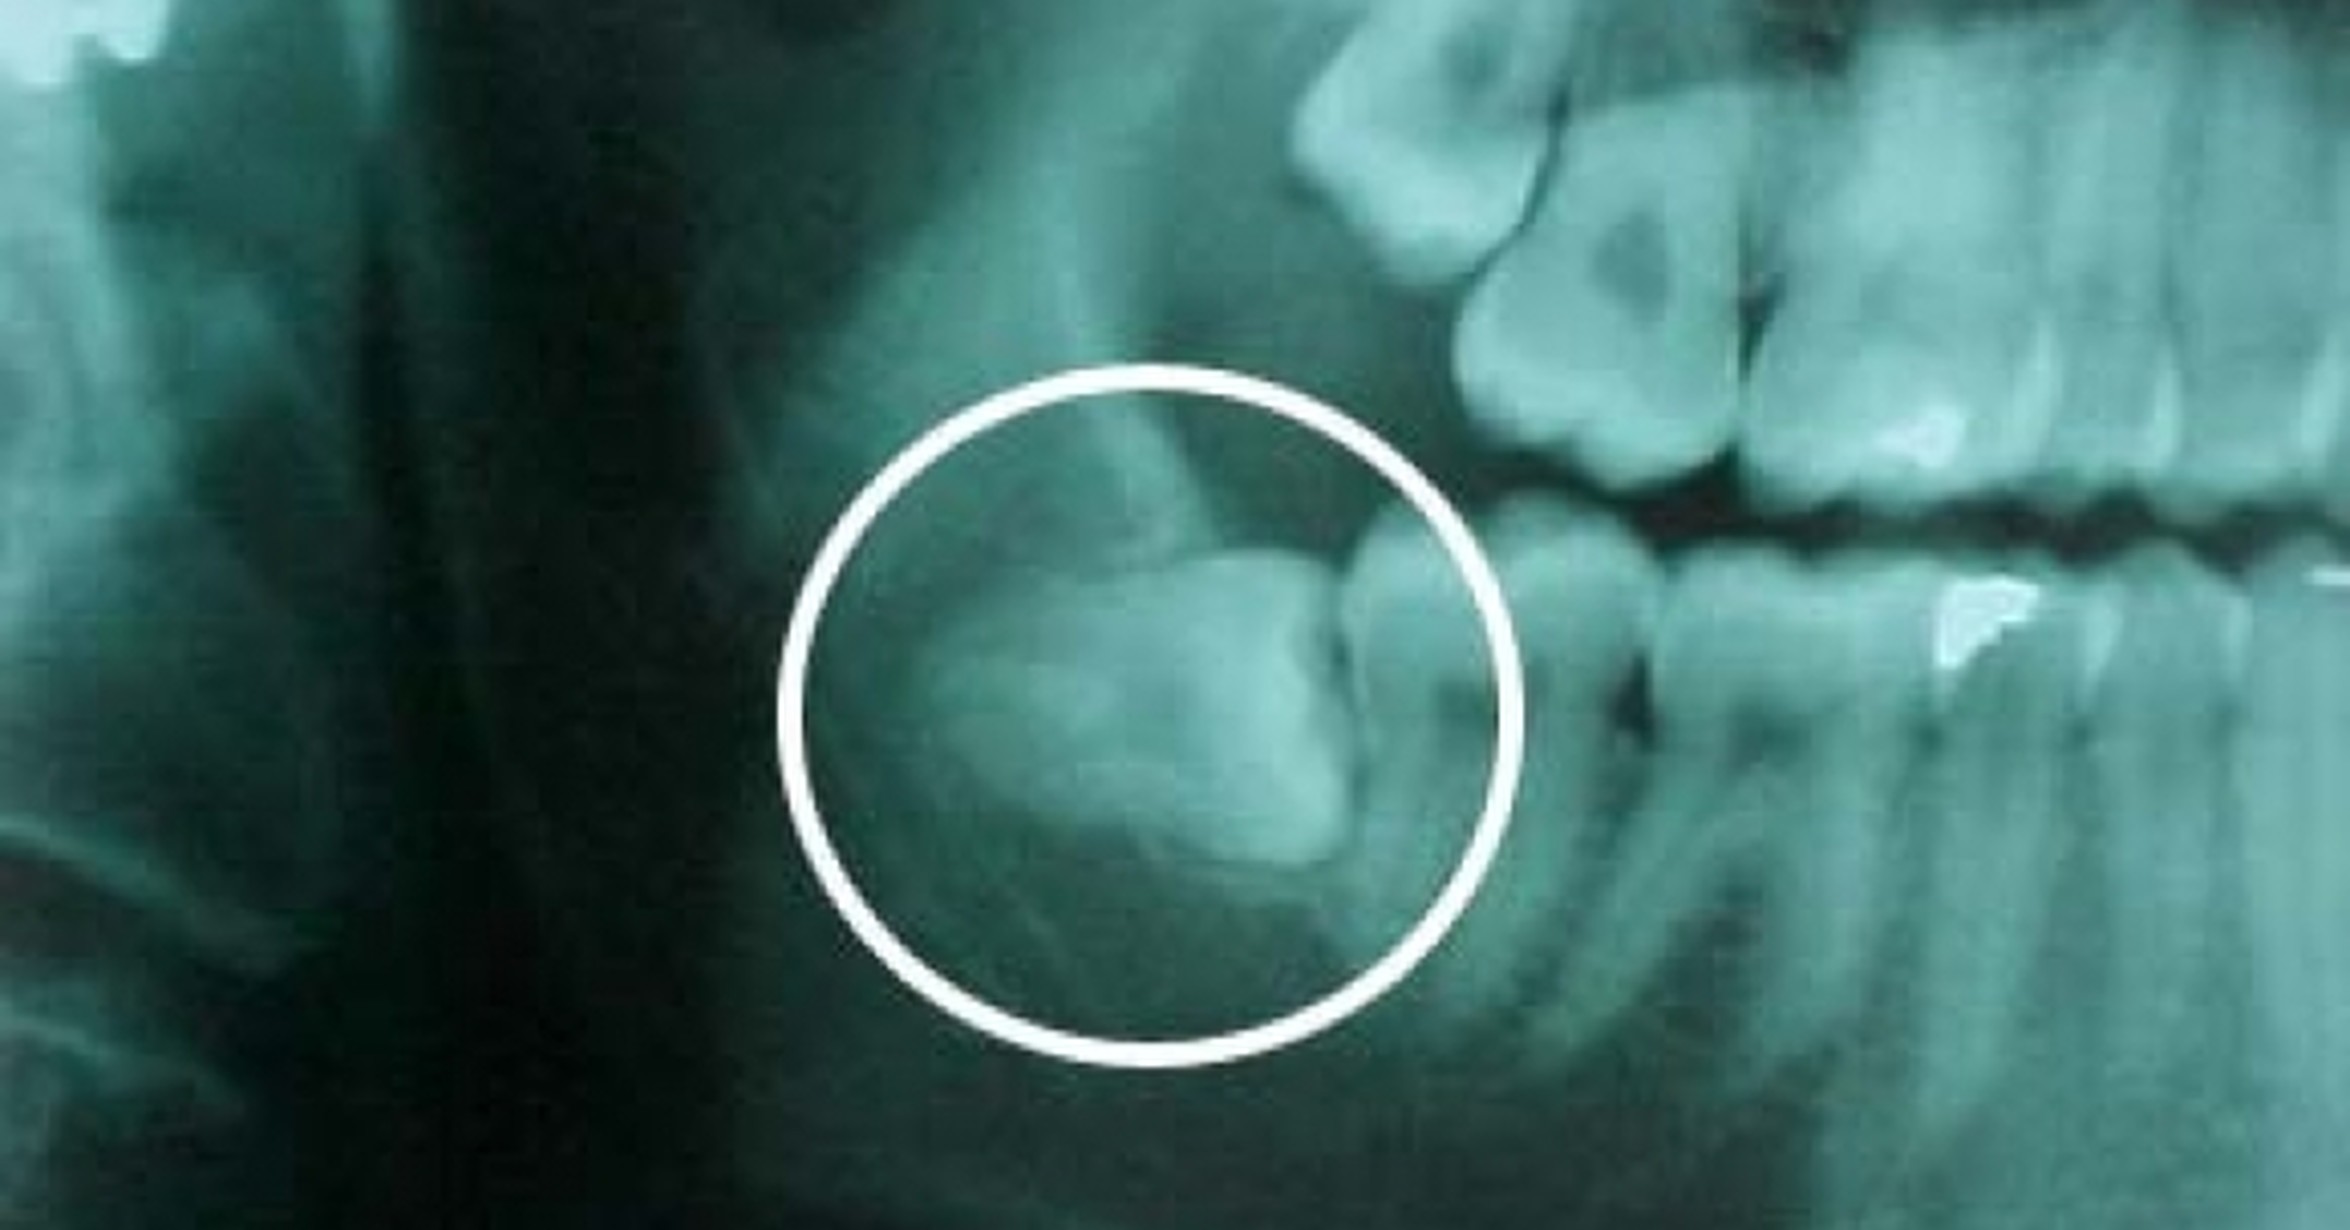

Прорезается Зуб Мудрости Фото

Прорезается Зуб Мудрости Фото 82 фотографий